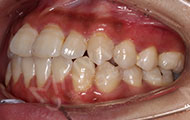

2017年10月18日 与麦芽的老朋友们谈笑风生

回老地方坐坐,找老朋友聚聚。矫正快一年了,牙齿渐渐开始整齐了,矫正效果不错哦~